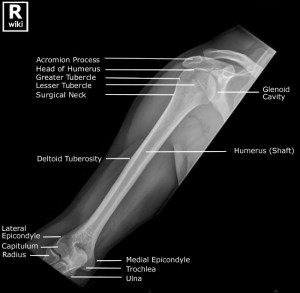

Above images from WikiRadiography (WetPaint) here.